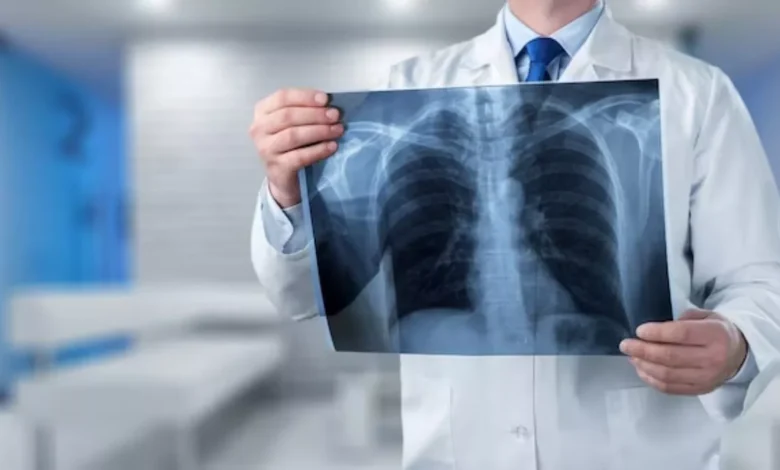

शरीर की अंदरूनी समस्याओं को पता करने के लिए कई तरह की तकनीक का प्रयोग किया जाता है। इससे मरीजों को सटीक जानकारी प्राप्त होती है और डॉक्टर्स को भी इलाज करने में मदद मिलती है। इन्हीं जरूरी टेस्ट में शामिल है रेडियोलॉजी। लोगों को इसके बारे में जागरूक करने के लिए हर साल 8 नवंबर को वर्ल्ड रेडियोलॉजी डे मनाया जाता है।

कई बार हम कुछ ऐसी बीमारियों के शिकार हो जाते हैं, जिन्हें पता लगाना मुश्किल होता है। इसके लिए कई तरह के टेस्ट करवाने पड़ते हैं। इन्हीं जरूरी टेस्ट में शामिल है रेडियोग्राफी। जिसकी मदद से शरीर की अंदरूनी समस्याओं के बारे में पता किया जा सकता है।

दुनियाभर में लोगों को रेडियोग्राफी के महत्व को समझाने के लिए यह दिन सेलिब्रेट किया जाता है। रेडियोग्राफिक इमेजिंग मरीजों के उपचार में महत्वपूर्ण भूमिका निभाती है। इसके जरिए शरीर के गंभीर बीमारियों के बारे में पता किया जा सकता है। यह किसी भी बीमारी के बारे में सटीक जानकारी देती है। रेडियोग्राफी थेरेपी के हर साल हजारों मरीजों की जान बचाई जाती है।